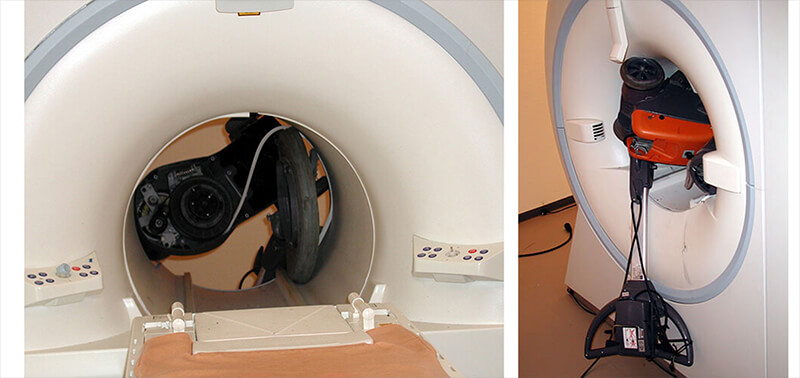

There are many things in a hospital or imaging center which can become dangerous projectiles in the MRI suite. The first two images (check below) show a floor polisher in a 1.5 T MRI room and the last four are a bed in a 3T MRI room. We can imagine the violence of the shock and, compared to the fourth video below, we see the difference in force with a 1.5 T machine. A patient was in the bed at the moment of the shock and fortunately there was only material damage.

This accident is relatively common and must be prevented especially when starting an MRI activity within an institution. At times, Safety rules are not well transmitted and if we add the curiosity of people to explore the machine closely, this increases the risk of accidents. For these reasons, it is essential that all staff who could potentially come into the MRI suite be screened and properly trained about the dangers of a very large, strong magnet.